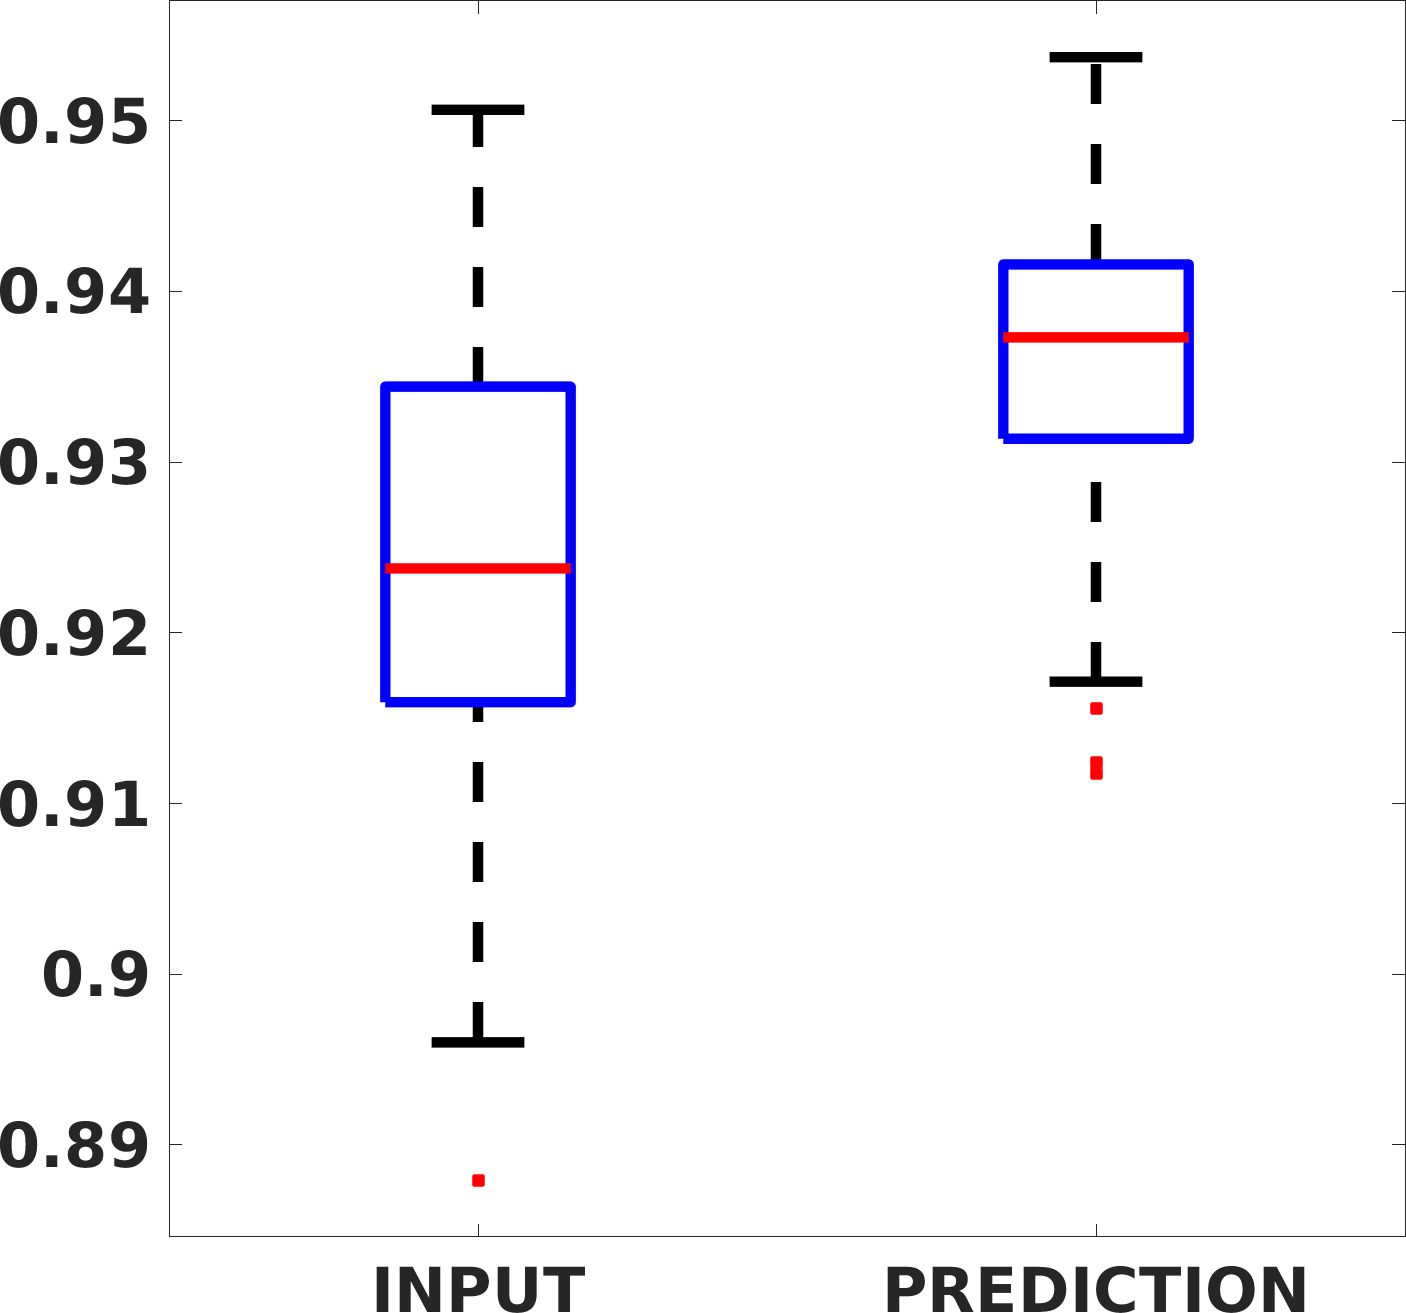

Fig. 7(a-b-c, left) shows the box plot of the statistics of the PSNR on three different anatomical districts, comparing the target images with the prediction and the cubic convolution, respectively. The metrics are computed on a data set of 200 images of the same district and with the same up-sampling factor. We report that the PSNR median value improves of on obstetric 2X raw images, on cardiac 2X raw images, and on abdominal raw 4X images.

Fig. 8 shows the box plot of the SSIM (a-b-c, left) and MAE (a-b-c, right) quantitative metrics, as performed for PSNR metric. Also, these metrics show that our method improves the results of Cubic convolution both in terms of average value and variability. For example, the SSIM median value improves of on obstetric 4X images and the MAE median value improves of on cardiac 2X images.

Fig. 17 (left) shows the box plot of the quantitative metrics, comparing the target images with the prediction and the Cubic convolution, respectively. The PSNR metric is computed on a data set of 200 images, belonging to the same district, and with the same up-sampling factor. Analysing the obstetric anatomical district and concerning the corresponding raw images (Fig. 7 (a, left)), the denoising allows the network to significantly improve the results of the up-sampling and the prediction. In particular, comparing the target images with the predicted images, the median PSNR value of obstetric 2X denoised images is 51.8, compared to the median PSNR value of obstetric 2X raw images which is 36.9.

Fig. 17 (right) shows the histogram of the absolute value of the error with respect to the target, of the prediction and Cubic convolution respectively. This result shows that our framework increase of and (2X and 4X, respectively) the number of pixels where the prediction error is lower than 5, which is very similar to the target when visually analysing the images, and improved with respect to the learning framework applied to raw images. According to Fig. 18, our method improves the accuracy of Cubic convolution. For example, the SSIM increases of on cardiac 2X and the MAE increases of on abdominal 4X.